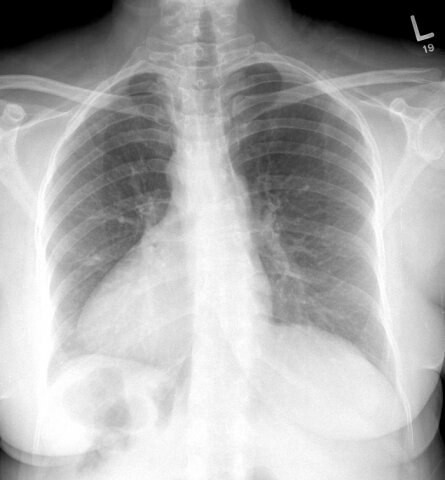

Астматический статус и декстракардия(сердце расположено справа)все стало на свои места! А "опытный" рентгенолог, теперь работает в одной из частных клиник нашей столицы!

P.S. вот так выглядит декстракардия,фото не мое.